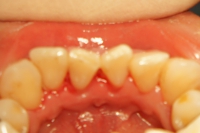

クリーニング・歯石除去

➡

歯の形が変わって見えるほど歯石が沈着しています。

除去後は歯石による炎症で出血してしまっています。

簡単なクリーニングでここまできれいになります。